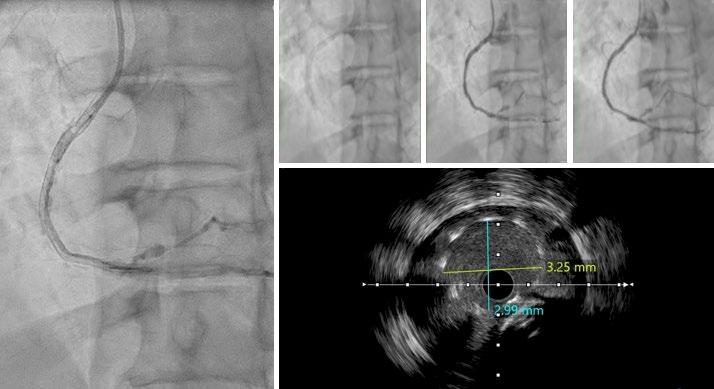

do a similar analysis in Europe, it's probably 80% receiving alcohol ablation, and if you go to Asia, the percentage undergoing alcohol ablations is even higher. In general, I think there has been a larger adoption of minimally invasive procedures in Europe and Asia, partly for spiritual reasons in Asia, and in Europe, I think it’s more due to lack of availability of surgical centres. Whereas, in the USA, there are many large centres that have shepherded hypertrophic cardiomyopathy care for many, many decades, and so surgery continued on as a primary modality. I do think that in the appropriate hands, the mortality rate is better and the efficacy is similar with alcohol ablation (in the appropriate patients), and so the only detriment really is the pacemaker rate. Mostly, patients over the age of 50 or 60 years typically don't mind this, because if they get a pacemaker at that age, it's usually not too much of a burden. It also allows monitoring of the patient for atrial fibrillation or other arrhythmias that might prevent sudden cardiac arrest down the line.

The problem with both of these procedures is that they are very hard to teach and, like any other procedure, you need to do a certain number of them to maintain the credibility and expertise over time. So, in the 2011 American Heart Association (AHA) guidelines, we recommended that institutions should do 10 procedures a year to maintain certification, credibility, and expertise, but very few places can do that. In our heyday, we were doing about 40 alcohol ablations and 30 myectomies a year here. Now, with the use of mavacamten and other cardiac myosin inhibitors, the volume of procedures done will be cut in half. So, one of the main challenges is,

how do you set up major centres to offer this? With this in mind, we developed a course. It's over 10 years old now; we had a break during the COVID-19 pandemic, but we've done roughly seven courses since its inception, and they have been very popular. The only way to learn this procedure is to see a few of them at once. We usually have about three cases over the course of 2 days, and then, through didactics, we discuss all of the alcohol ablation details, including preprocedural and intraprocedural planning and post-procedure management. We then take attendees through live cases, where we go through the procedure step-by-step on actual patients. Finally, we end with critical care rounds, where we look at the patients afterwards and discuss their ECG, pacemaker requirements, and how to manage them before they go home. It's a very comprehensive course and we’ve probably trained over 100 people who have all gone out to do the procedure. So, it does work and now they have the experience. Even if they don't do 10 per year, they have a network of individuals who they can run cases by and refresh their ideas on the tools and the equipment needed, and how to plan for that procedure for that given patient.

I do think that surgeons should do the same thing. They have not developed a course in this space. I have advised that they do because I think that both these procedures are very important and valuable for the population, including in Europe. About 10 years ago. Barry Maron wrote a paper entitled, ‘Bring Septal Myectomy Back for European Patients’,1 which was essentially a call to action, highlighting that we do need capable surgeons out there to do this. I would be an advocate for that as well.

In the surgery field, they train in their fellowships, but then afterwards there's not a whole lot of training opportunities, from what I can see. I think it's more in the mindset of interventional cardiology to proctor other people and spread these procedures more broadly. But I think within the surgical field, they tend to rely on their societies and their training pipeline, and not necessarily courses like these. Additionally, they tend not to train their competition. Now, you can say the same thing for interventional cardiology, but I specifically bucked that trend by saying: “I'm going to train people to compete with me.” That’s because the greater good is more important. I know it's easy to say that, but the truth is that in any field, people tend to hold on to their trade secrets. Now, with that being said, I will say that our surgeons were trained by the Mayo Clinic surgeons, but that was through a personal relationship. Though I think the Mayo Clinic surgeons have done a good job of going out and training individual surgeons at other institutions, and I give them credit for that, I do wish that somebody would take the mantle and develop an actual course. We did think about expanding our course to include surgeons, but again, it depends on funding and the availability of surgeons who are willing to do it.

Q3 Can you tell us about your book, ‘Lindsay's Big Heart’. How does improving patient/family health literacy correlate with treatment adherence and outcomes in the HCM population?

I'm a creative person; I like doing different things and coming up with new ideas. This idea came out of a desire to spread HCM awareness a lot broader, and

books have a way of spanning globally. In other words, they can be translated to other communities. And actually, we've had some interest from the HCM Foundation in Europe, as well and other places, to translate the book.

The reason for spreading awareness for HCM is that most patients with HCM seek medical attention when they are middleaged, which means that they have probably been living with their HCM for decades. It's known to start in puberty and teenage years, so there's usually a long latency period where they have the disease but no symptoms. We would like to catch people at that stage where they're developing hypertrophy but don't have symptoms, so we can start getting them treated earlier and possibly prevent progression.

The second issue is that a lot of these people have kids, and they have no idea how to talk to their kids about this disease. I feel like if a woman has breast cancer, they sit their daughter down, tell them about breast cancer, and why they need to have mammographies. However, we don't do the same for other genetic diseases, like HCM, and because of that, I wanted to have a tool that parents can read to their kids while they're young, before the HCM even develops, if it even develops. That way,

when they get older and their ECG looks suspicious or they have symptoms, they will not be scared to tell their doctor that there is HCM in their family. At the moment, I do not see that happening, and the only way to get that to happen is to educate people at an age where they can see that this is running in their family and not be scared of it. That's the second part of it, which is something the book really addresses: how to digest this disease as one thing in your family and not be scared of it.

We would like to catch people at that stage where they're developing hypertrophy but don't have symptoms

What you see is a young girl go through this and lead a very happy, normal life. It shows that none of the testing was scary, and she can go on to do all the things she wants to do; she just happens to have this bigger community of physicians, parents, and other people who now know her and how to protect her, including having defibrillators in the school and people around her knowing CPR. So, I think the

book comes out of this genuine idea to have a resource for kids where they can be curious and understand their disease in a way that makes sense to them.

At the same time, we didn't want to water the information down. We made sure that the book has pictures that are accurate, and every picture included has educational value, including having defibrillators visible and showing the different testing that people get throughout their evaluation and management. I spent a lot of time on additional pages for parents at the end: two pages on how to keep your kids safe, and two pages that define all the complicated medical terms that even parents wouldn't understand, so that they're prepared when they go into their doctor's appointment. So, there's a little bit of a dictionary at the end to help people understand the top 20 words that come up in this disease. I wanted to make sure the book really spanned both parents and kids.

If we have the energy and funding, we would like to translate the book into different European languages, certainly Spanish and French, and then eventually Mandarin and Arabic. I'm not sure what else, but those probably cover a large portion of the world. HCM is a disease that spans both genders and all races, and happens

in rich communities and poor communities; I do want to get it to all kids of the world. A 19 USD book is something that you can get everywhere, including for free in libraries, whereas actual healthcare is not quite as egalitarian.

Are you planning on writing any other books?

I’m not writing any at the moment, because I have a lot on my plate right now, but the publisher that we have has already mentioned that they would love to have more of a series. Lindsay Davis is one of my friends with HCM and this book is modelled after when she was around 8 years old, and Kiran, the boy in it, is my son, and it's modelled after when he was also 8 years old. He's sort of the ‘smarty pants’ kid who teaches her a lot whilst in the hospital after having a false alarm. So, I think one of the ideas was to have a Lindsay and Kiran series, where they can each be the protagonist, depending on the disease state. For example, the next book could be about Kiran's peanut allergy. There's so much opportunity to talk about something like that and make different conditions and diseases less scary.

Q4Your work on the 2019/2022 universal cardiogenic shock definitions revolutionised trial design. How have these criteria impacted mortality stratification in recent studies like RECOVER III?